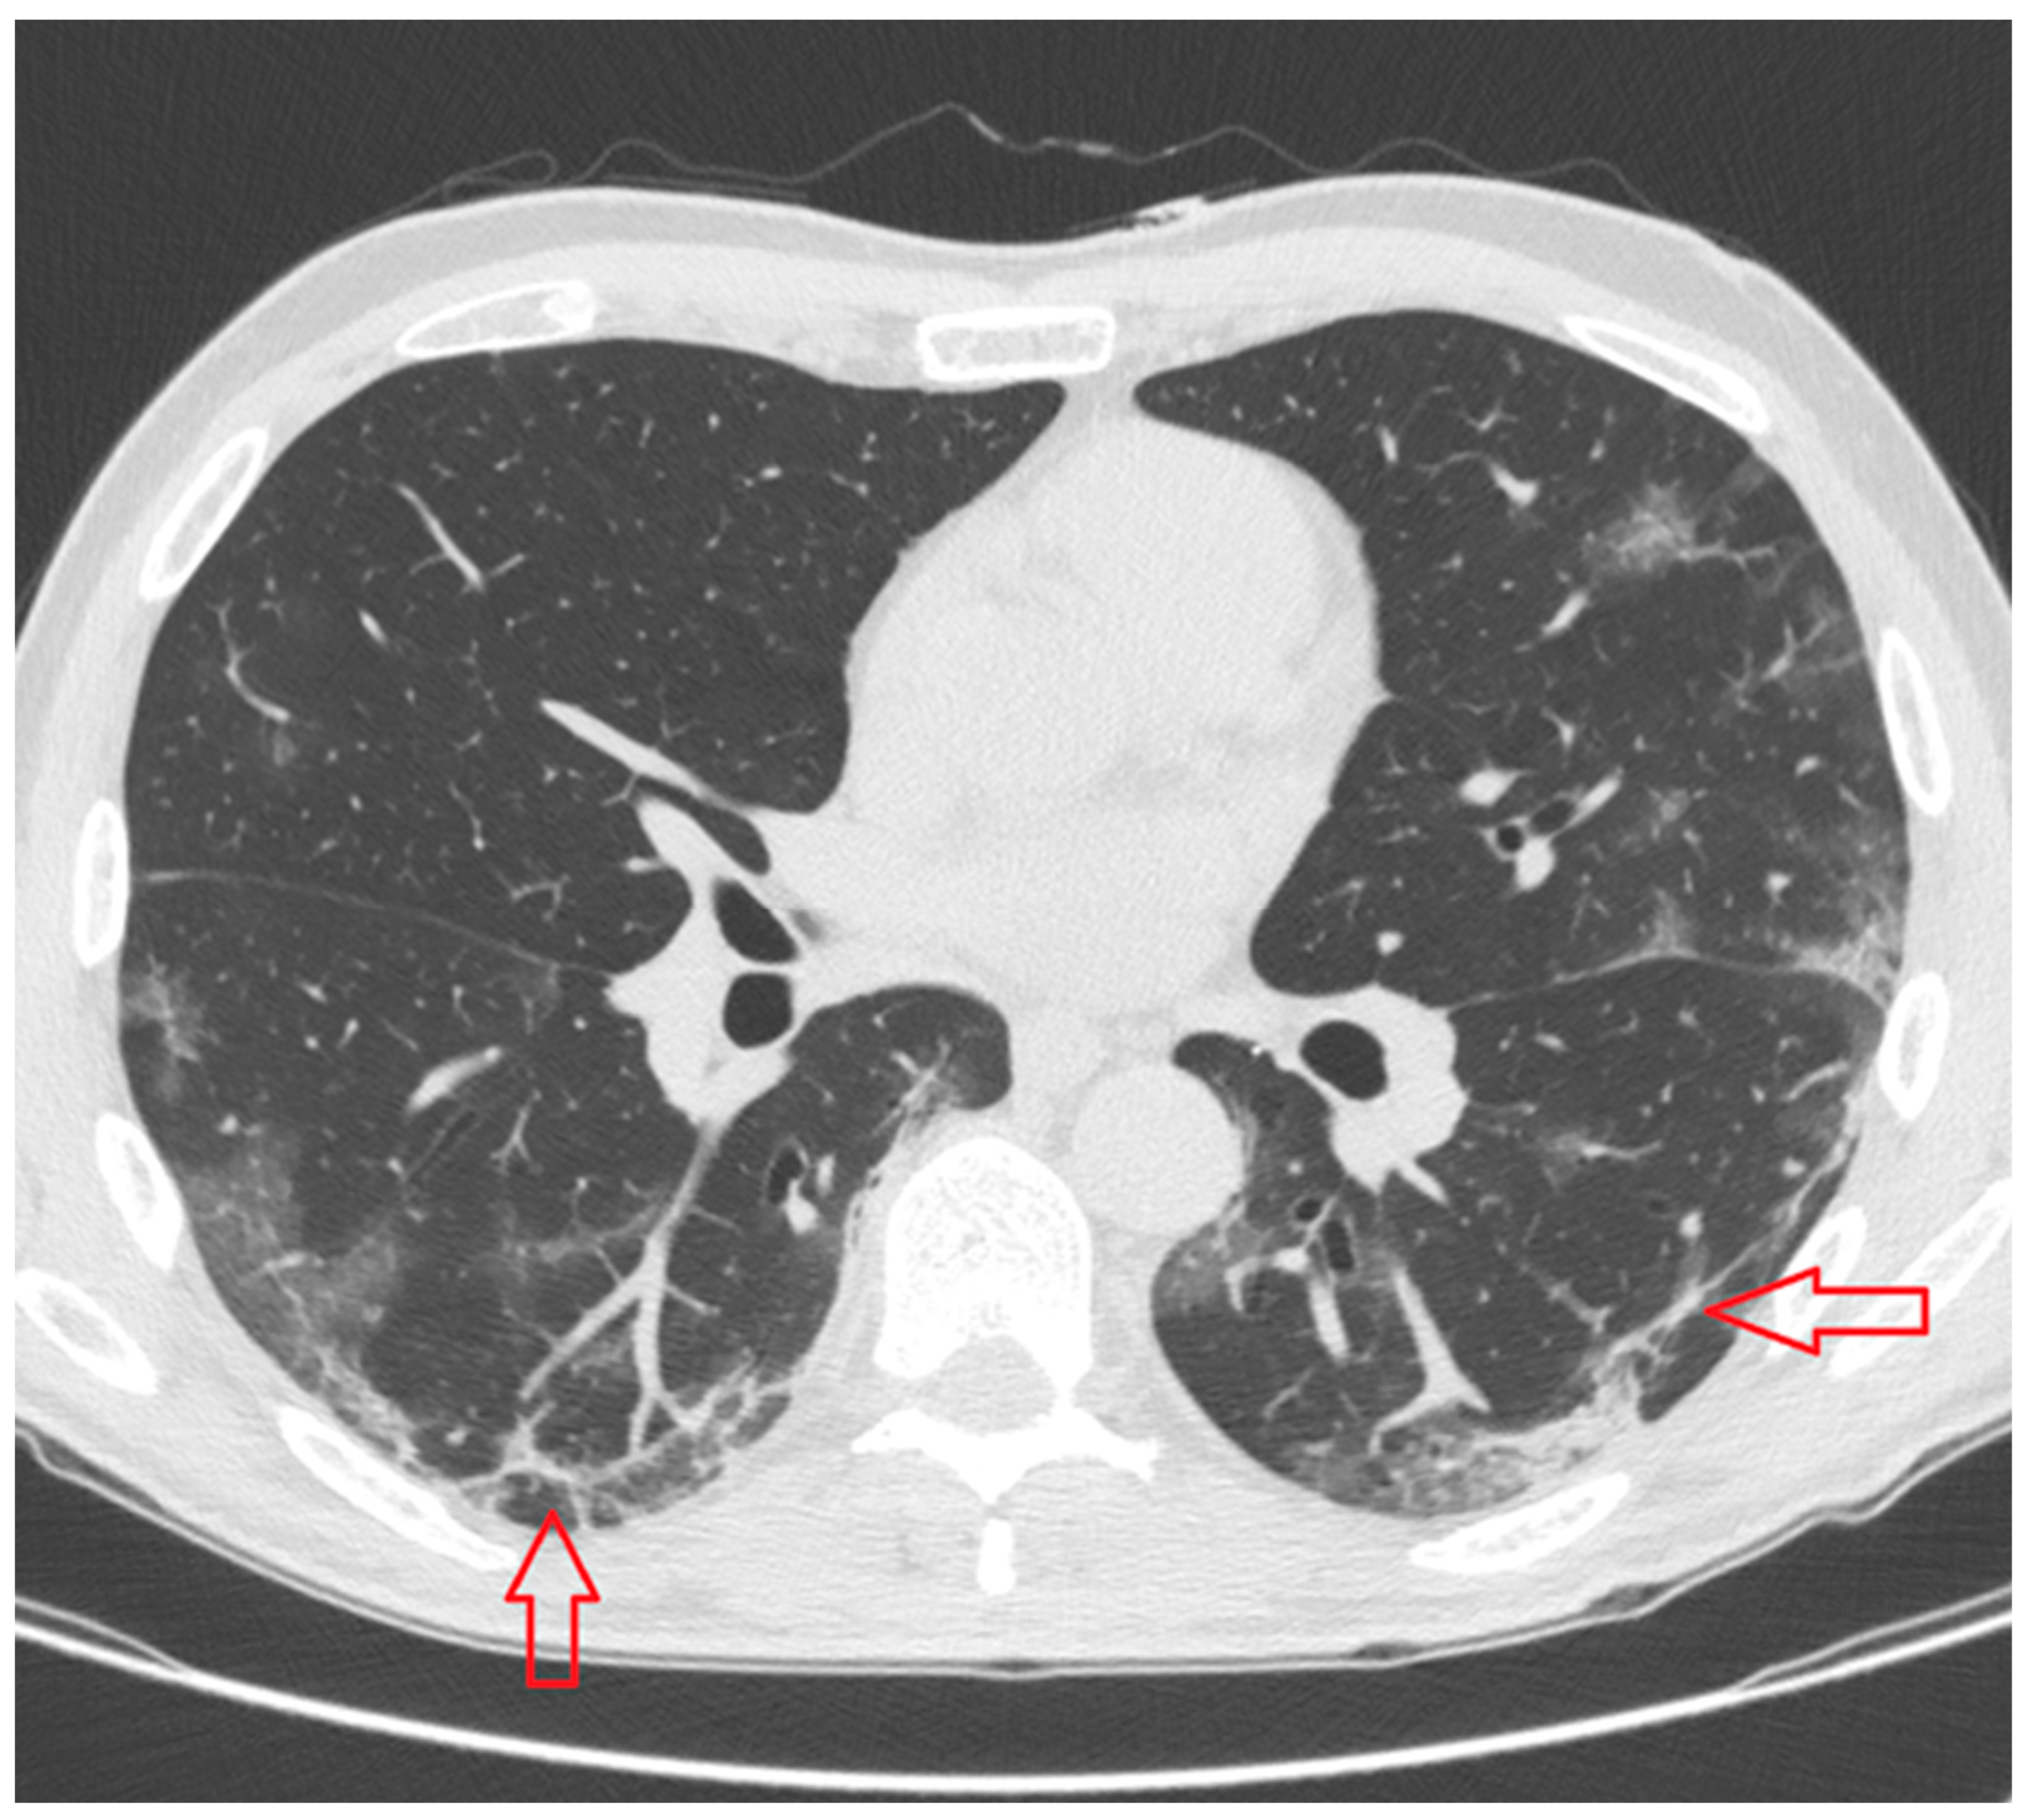

- Crazy paving pattern: thickened interlobular septa and intralobular lines superimposed on a background of ground glass opacity (Figure 5);